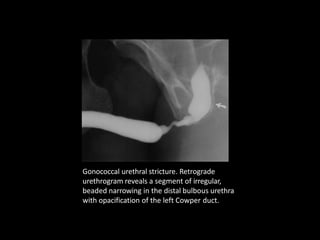

Gonococcal urethral stricture. Retrograde

urethrogram reveals a segment of irregular,

beaded narrowing in the distal bulbous urethra

with opacification of the left Cowper duct.